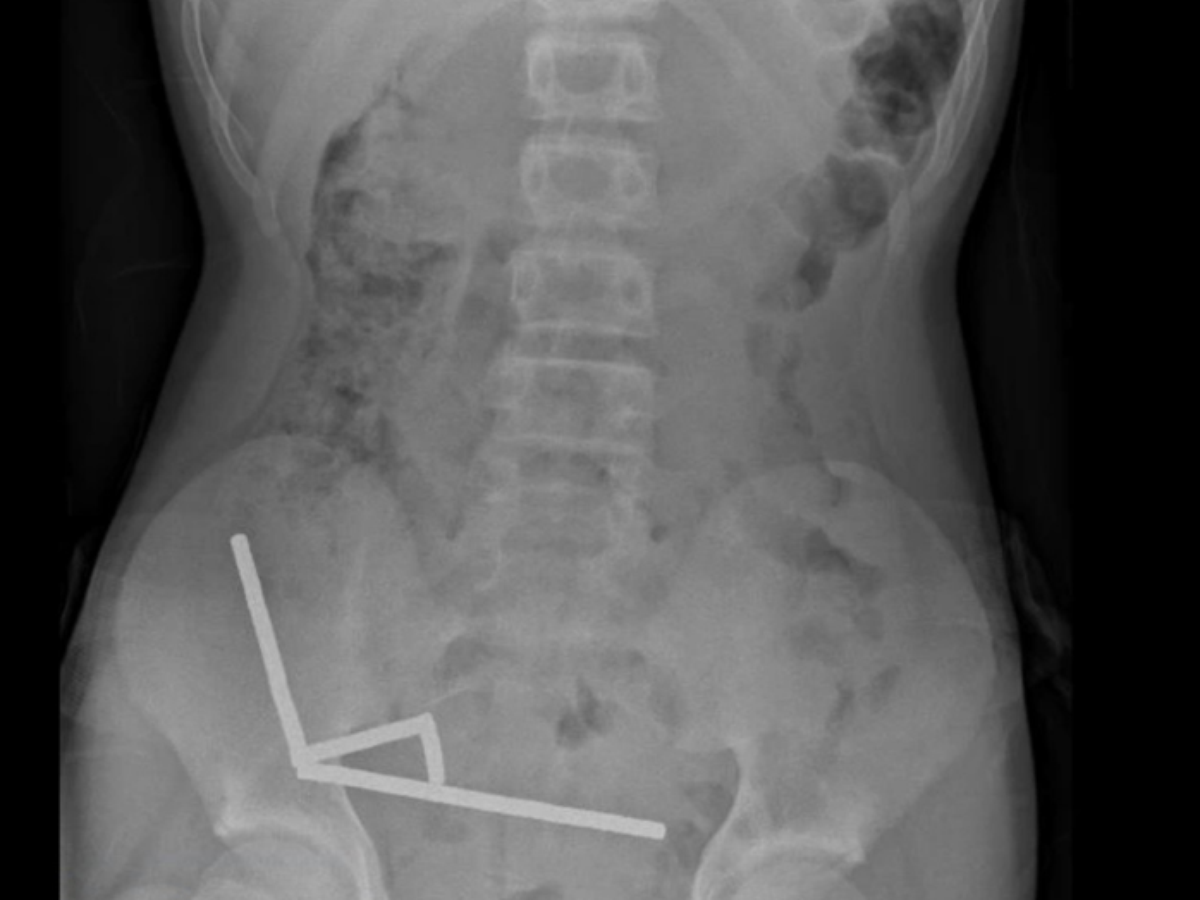

Raio-x mostra ímãs no intestino de garoto na Nova Zelândia

Foto: Reprodução/New Zealand Medical Journal

Por meio de exame de raio-x, os profissionais detectaram quatro ‘linhas’ de ímãs no intestino do garoto. No intestino, devido à força magnética, os objetos se uniram uns aos outros.